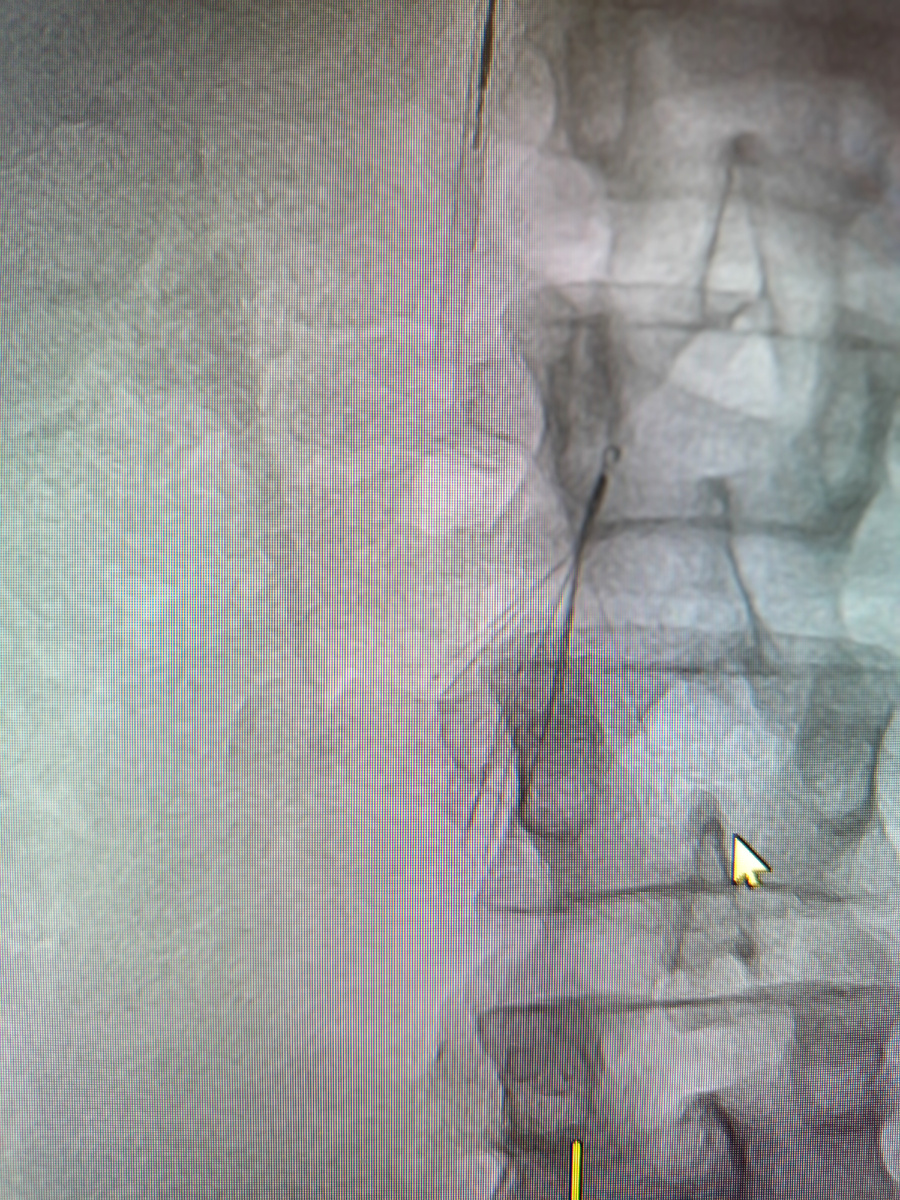

Кава -фильтр ставят для профилактики ТЭЛА. У нас кава-фильтры в виде зонтика, они так и называются.

Сама операция недолгая. Доступ осуществляется через яремную вену, потом заводятся проводник, по нему катетер, выполняется флебография.

Визуализируют тромб, а потом по проводнику заводят систему , с этой ловушкой, все , зонтик остается в сосуде.

Через три недели нужно делать флебографию повторно, и если ловушка поймала тромб, то ее не вытаскивают, а если пустая, то зонтик извлекают.